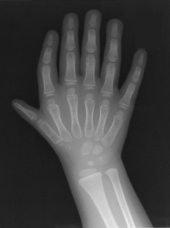

Triphalangeal thumb

First described by Columbi in 1559,[1] triphalangeal thumb (TPT) is a congenital malformation where the thumb has three phalanges instead of two. The extra phalangeal bone can vary in size from that of a small pebble to a size comparable to the phalanges in non-thumb digits. The true incidence of the condition is unknown, but is estimated at 1:25,000 live births.[2] In about two-thirds of the patients with triphalangeal thumbs, there is a hereditary component.[3] Besides the three phalanges, there can also be other malformations.

The triphalangeal thumb has a different appearance than normal thumbs. The appearance can differ widely; the thumb can be a longer thumb, it can be deviated in the radio-ulnar plane (clinodactyly), thumb strength can be diminished. In the case of a five fingered-hand it has a finger-like appearance, with the position in the plane of the four fingers, thenar muscle deficiency, and additional length. There is often a combination with radial polydactyly.